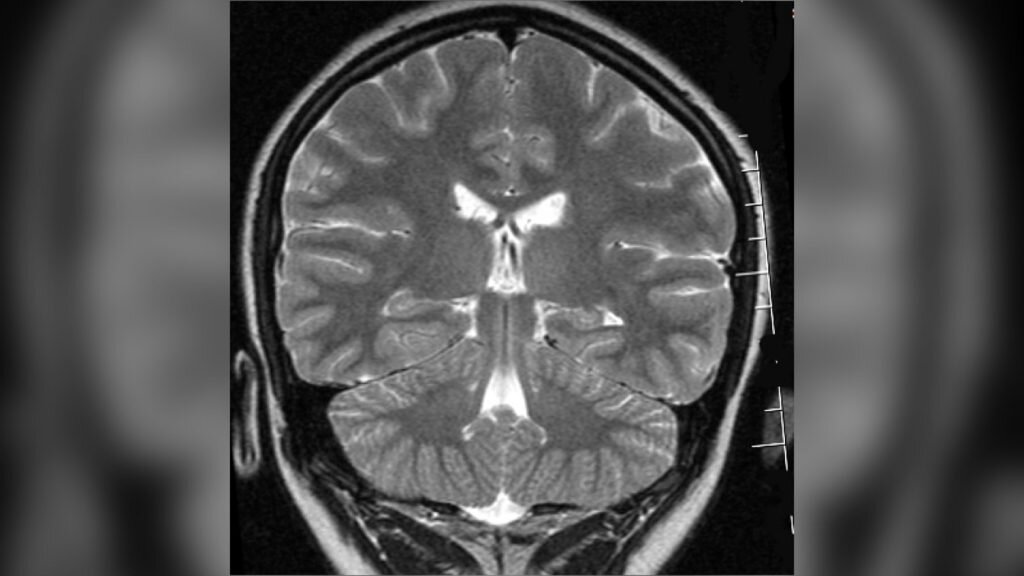

Изображения и схемы глубокой стимуляции мозга